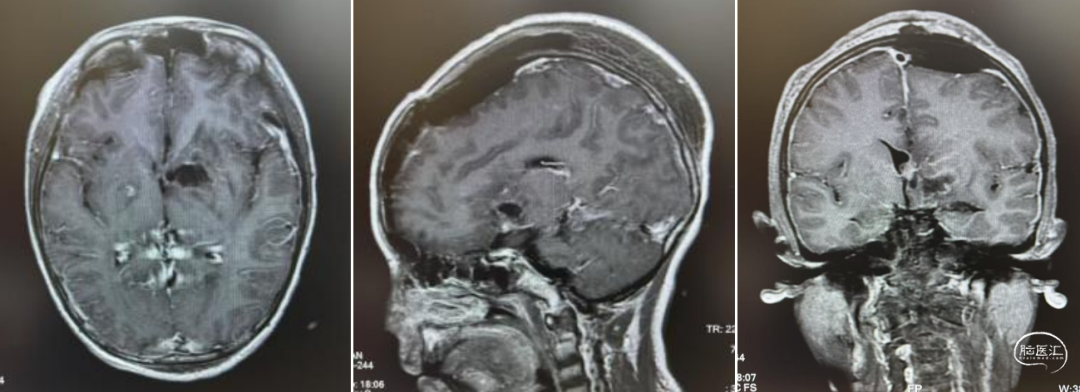

头部MRI显示:鞍区-鞍上区-双侧额叶-胼胝体前份可见一不规则形等-长T1等-长T2信号囊实性团块灶,FLAIR呈等-稍高信号,DWI示实性部分稍高信号,相应ADC低值,增强扫描病灶实性部分明显强化;邻近脑实质见片状FLAIR高信号,双侧侧脑室前角受压,中线结构无移位,脑沟、脑裂未见明显增亮。松果体区见环形强优结节,直径约9mm。

经儿童脑肿瘤MDT讨论后,建议先化疗再放射治疗。1疗程后病变明显退缩,甲胎蛋白(AFP)、人绒毛膜促性腺激素(β-HCG)降至正常范围。结疗后复查,肿瘤完全消失,无复发。此后1年予以定期复查未见复发。

1疗程后评估